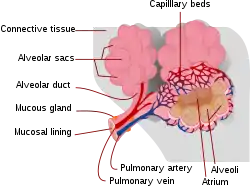

Respiratory zone

The conducting zone of the respiratory tract ends at the terminal bronchioles when they branch into the respiratory bronchioles. This marks the beginning of the terminal respiratory unit called the acinus which includes the respiratory bronchioles, the alveolar ducts, alveolar sacs, and alveoli.[29] An acinus measures up to 10 mm in diameter.[30] A primary pulmonary lobule is the part of the lung distal to the respiratory bronchiole.[31] Thus, it includes the alveolar ducts, sacs, and alveoli but not the respiratory bronchioles.[32]

The unit described as the secondary pulmonary lobule is the lobule most referred to as the pulmonary lobule or respiratory lobule.[27]: 489 [33] This lobule is a discrete unit that is the smallest component of the lung that can be seen without aid.[31] The secondary pulmonary lobule is likely to be made up of between 30 and 50 primary lobules.[32] The lobule is supplied by a terminal bronchiole that branches into respiratory bronchioles. The respiratory bronchioles supply the alveoli in each acinus and is accompanied by a pulmonary artery branch. Each lobule is enclosed by an interlobular septum. Each acinus is incompletely separated by an intralobular septum.[30]

The respiratory bronchiole gives rise to the alveolar ducts that lead to the alveolar sacs, which contain two or more alveoli.[22] The walls of the alveoli are extremely thin allowing a fast rate of diffusion. The alveoli have interconnecting small air passages in their walls known as the pores of Kohn.[22]